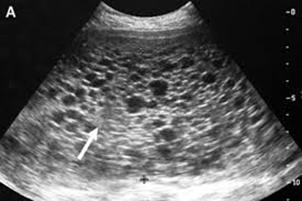

La ecografía del II trimestre (20-24 semanas) permite el diagnóstico morfológico (biometría fetal), importante para detectar malformaciones de los diferentes órganos y sistemas. Los defectos más fácilmente detectados son del sistema genitourinario y de tubo neural. Las cardiopatías hoy en día no son difíciles de diagnosticar. La tasa de detección de cardiopatías puede llegar a ser entre 60 a 80%. El higroma quístico corresponde principalmente a una malformación del 2do trimestre que se asocia con síndrome de Turner (monosomía 45, X0).